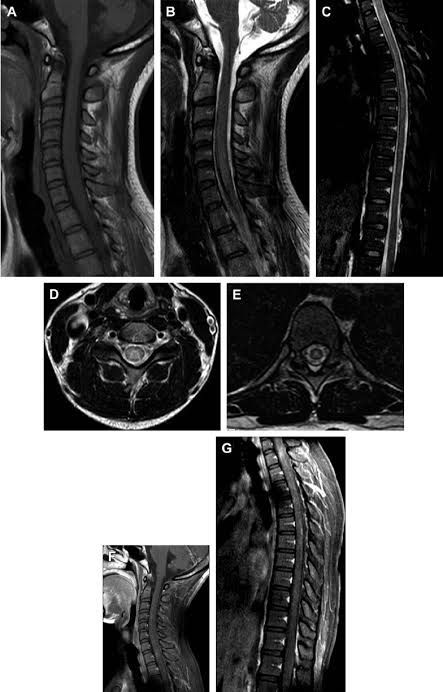

General unspecific symptoms were identified in almost all cases, with high frequencies of fever (78.9%) and lymphadenomegaly (36.8%). Six patients had skin lesions (31.5%); six arthralgia or arthritis (31.5%) and eight neurological symptoms (42%).